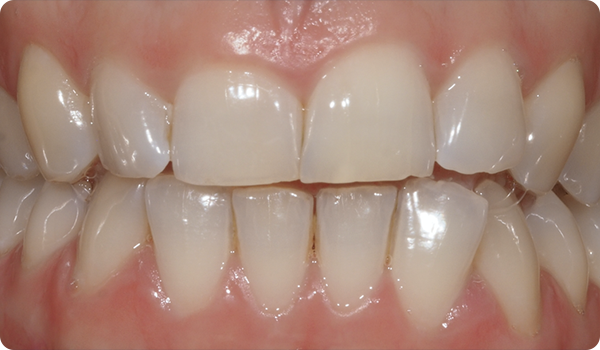

Leenden på plats

Med Right får dina patienter det leende de önskar, inom den tid de vill, på ett bekvämt och ”osynligt” sätt.

Att justera tänder med Right är den perfekta och mest konservativa grunden för framtida blekning eller facettbehandlingar som kommer att föra patientens leende till perfektion.